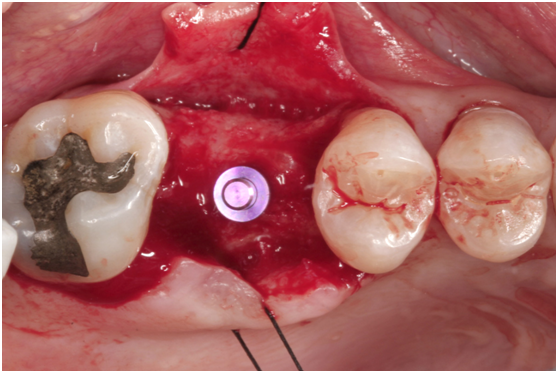

於100/06/07重新放置兩顆植體

並於100/10/25將中間兩顆植體做二階接出

由於前後植體的高低差距太大,決定將中間兩顆高度較為一致的植體假牙做連結,但前後兩顆做單顆假牙的設計。

100/11/21 補綴完成